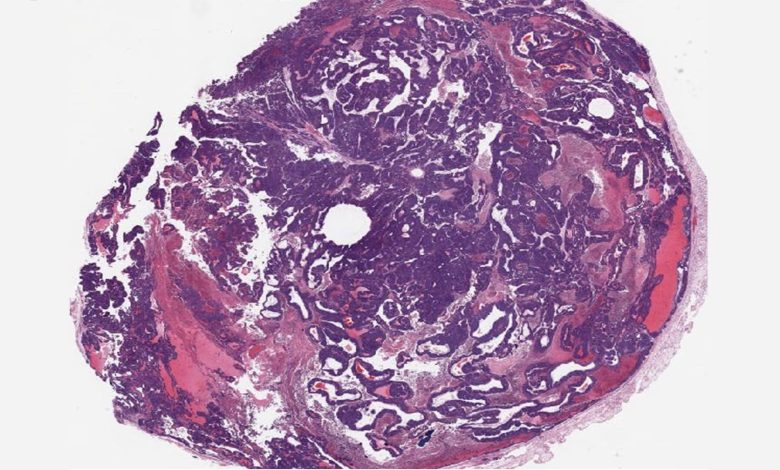

Um tumor mamário de um camundongo knockout para BPTF; animais com níveis mais baixos desta proteína tiveram menos metástases de câncer e viveram mais do que aqueles com níveis normais de BPTF. Crédito: laboratório dos Santos/CSHL

Conhece alguém que foi diagnosticado com câncer de mama? Há uma boa chance de que essa pessoa tenha recebido terapia hormonal. Os cânceres de mama positivos para receptores de estrogênio (ER+) representam cerca de 75% dos casos. A terapia hormonal é um dos tratamentos mais comuns e eficazes. No entanto, está longe de ser uma cura.

Uma pesquisa do laboratório da professora associada Camila dos Santos do CSHL mostra que a inibição da proteína BPTF em camundongos pode retardar a metástase do câncer ER+ e restaurar a suscetibilidade dos tumores à terapia hormonal. O estudo está publicado na revista Comunicações da Natureza.

No entanto, Ciccone e seus colegas de laboratório, o estudante Dhivyaa Anandan e o pós-doutorado Deeptiman Chatterjee, viram um potencial inexplorado. Para saber mais, eles criaram um modelo clássico de camundongo com câncer de mama com um camundongo knockout BPTF. Para sua surpresa, eles descobriram que os tumores nos camundongos mestiços permaneceram ER+ durante todo o seu desenvolvimento.